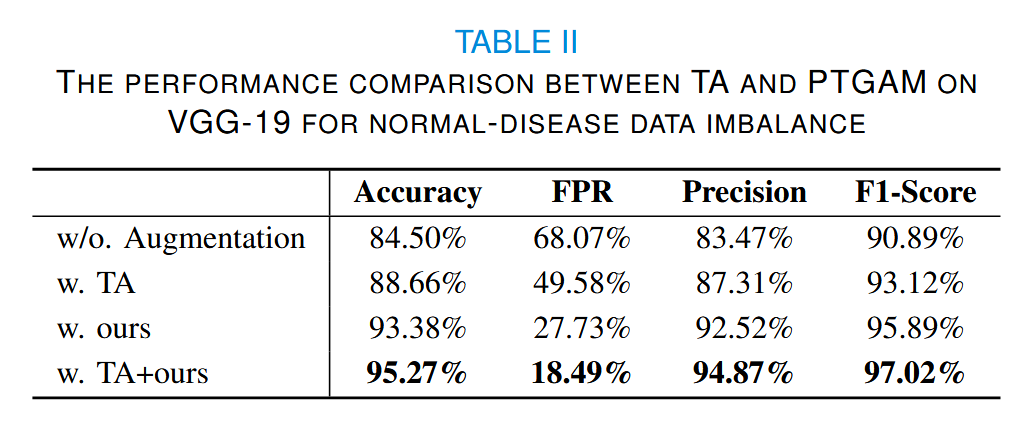

我们还进行了数据增强实验,并与TA进行了对比,如表II所示。

我们使用生成数据将训练集平衡至接近的数量,如图5(b)所示。

在良性数据稀缺的情况下,模型倾向于陷入偏向恶性类别的局部最优解。因此,我们选择假阳性率(FPR)和精确率来衡量不同增强方法的效果。可以看出,我们的方法能够显著减少假阳性。

当恶性数据稀缺时,我们选择假阴性率(FNR)和NPV。结果表明,当我们的方法与 TA 结合时,可以获得最高的准确率。然而,在FPR和FNR方面,我们的方法最大限度地减少了数据偏差的不良影响。